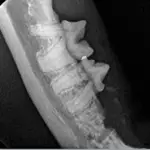

Step 11

An postoperative intraoral dental radiograph shows that the mesial root has been removed and the alveolar crestal bone over the distal root has been smoothed.